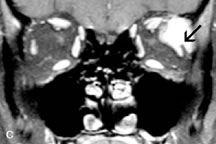

Inflammatory and Lymphoproliferative Lesions

Inflammatory conditions of the orbit, both idiopathic (inflammatory pseudotumor) and those of known causes, have been found to be hypointense to fat and isointense to muscle on Tl-weighted studies and isointense or slightly hyperintense to fat on T2-weighted images (Fig. 21).50,64,69 The more fibrous or sclerosing varieties have less signal intensity on T2-weighted images. Marked enhancement is seen in pseudotumor infiltrates after gadolinium administration.70 The same signal characteristics are demonstrated in patients with Tolosa-Hunt syndrome, with mass lesions seen in the cavernous sinuses and orbital apices.71

Fig. 21. A. T1-weighted MR scan demonstrates diffuse enlargement of both the superior rectus and levator palpebrae superioris muscles (single arrows). The involvement of the tendinous insertions and preseptal soft tissues (open arrows) as well as lack of involvement of other muscles helps differentiate this entity from thyroid-associated orbitopathy. B and C. Postcontrast fat-suppressed T1-weighted MR scans demonstrate extensive enhancement of the involved muscles as well as the preseptal (open arrows) and perinuscular tissues (double arrows).